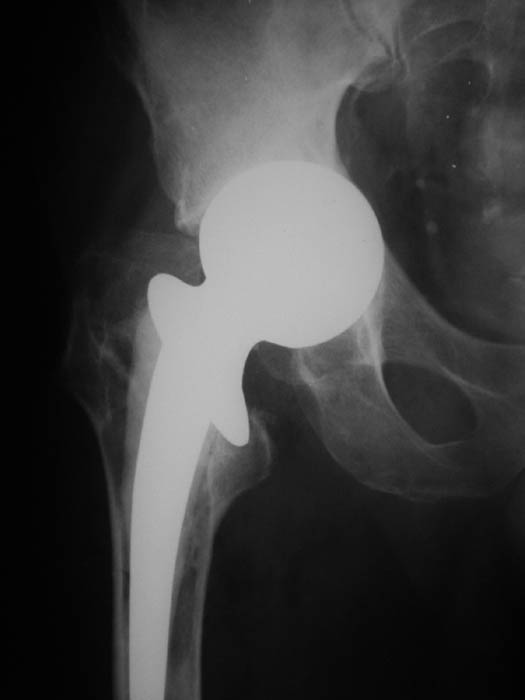

Мужчина, 77 лет. В 2000 г. по поводу субкапитального перелома шейки бедренной кости произведена операция эндопротезирования головки. На последних рентгенограммах обнаружена протрузия головки эндопротеза.

В настоящее ведет активный образ жизни, продолжает работать.Предполагается замена протеза на тотальный ревизионный. Интересуют предложения по восстановлению костной массы вертлужной впадины.Заранее благодарю!С уважением,А.В.ВладзимирскийДонецкий НИИ травматологии и ортопедииДонецк, Украина